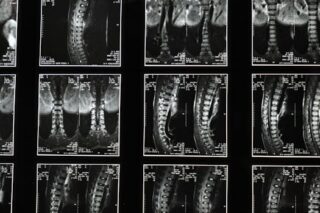

Dens fracture symptoms may include neck pain, limited mobility, and neurological signs such as tingling or weakness if the spinal cord is involved. Diagnosis typically involves imaging studies like X-rays, CT scans, or MRIs to assess the extent of the injury.

They are typically diagnosed using imaging techniques such as X-rays, CT scans, or MRIs to determine the fracture’s nature and extent.